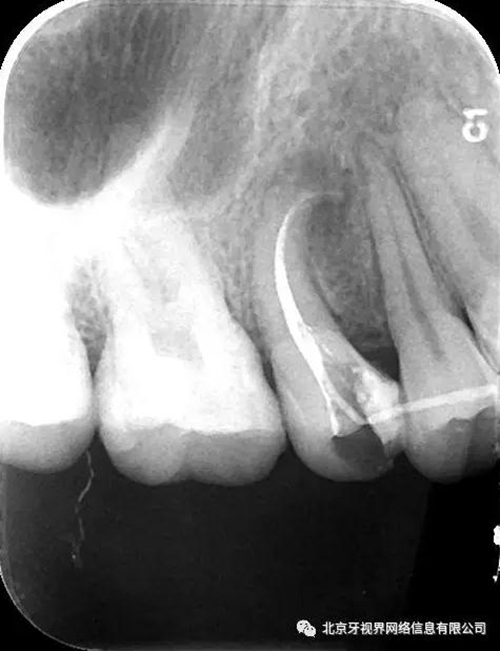

15備洞,揭頂,10#擴(kuò)大器預(yù)彎后疏通至全長(zhǎng),次氯酸鈉加超聲蕩洗,氫氧化鈣糊劑封藥,玻璃離子暫封,隨診。

2次復(fù)診常規(guī)根備加根充(AH-plus糊劑加牙膠尖根充)

4.此例病例中,術(shù)前分析后,采取先解放其中上段后,10#擴(kuò)大器預(yù)彎緩慢前行,抵達(dá)根尖區(qū)。

最后附帶近期彎曲根管的圖片